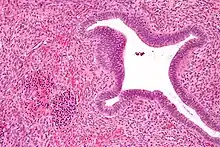

During the postnatal period, the spleen becomes a frequent site of EMH whereas, during the embryonic stages of hematopoiesis, it is only a minor factor. Despite the hypoxic/acidic conditions of the splenic microenvironment, supplied with a legion of macrophages making it inhospitable for HSCs, EMH usually occurs within the red pulp. Among the various organs associated with EMH, the spleen offers a unique site for evaluation of hematopoietic stem cell (HSC)/niche interactions.[12][11]

It is normal for infants have hepatic EMH as they are developing up until roughly 5 weeks of age.[13] On the other hand, hepatic EMH in adults can indicate a pathological state. This includes transplantation, hepatic tumors, hepatic disorders, or sepsis. Hepatoblastoma, adenomas and hepatocellular carcinomas can also lead to EMH in adults.[14][15] Additionally, EMH is often observed within the hepatic sinusoids.